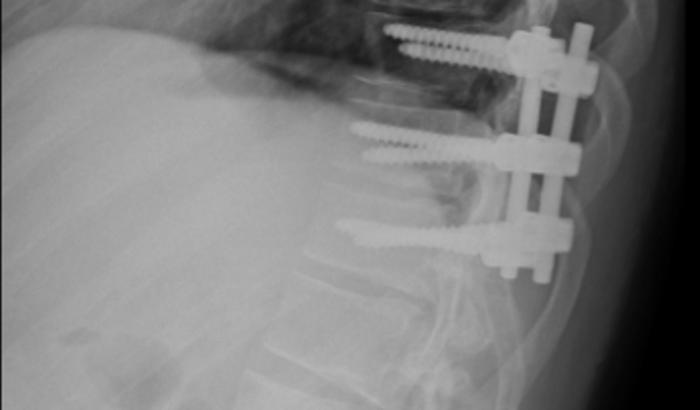

Tenho 31 anos, sou casado, pai de 2 crianças lindas, a Julia de 09 anos e o Gabriel de 09 meses. Estou com um problema na coluna, com indicação cirurgica, a qual estava agendada para 06/06/2022, porém precisou ser adiada devido a novos exames necessários, pelo quadro de piora. Algumas hérnias "romperam", causando grande compressão na medula, me causando muita dor, desconforto, e limitando muito a força e movimento das minhas pernas. Estou afastado do meu emprego, ao qual não consigo mais exercer a função devido a dor, desconforto e imobilidade das pernas, precisando usar muletas para andar e evitar novas quedas. Me encontro medicado, aguardando realização dos novos exames para definição da cirurgia. Infelizmente, minha perícia ficou marcada somente para 10/08/2022 e até lá, estou sem nenhuma fonte de renda, e a preocupação bateu. Minha esposa está sem trabalhar, pois como falei, temos um menino de 09 meses, que ainda nao vai a creche. Contas, remédios, tratamento, escola, exames que não possuem cobertura pelo plano de saúde, e o pós operatório que também será necessário. Ontem durante nova consulta médica, foi constatado que somente as hérnias não seriam capazes de estar fazendo todo esse diagnóstico, sendo necessário investigação mais apurada e com extrema urgência, devido a piora diária do quadro de movimento das pernas.Meu Pix: CPF 07629493924